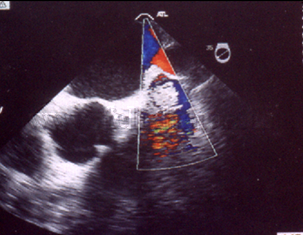

Cáncer de pulmón